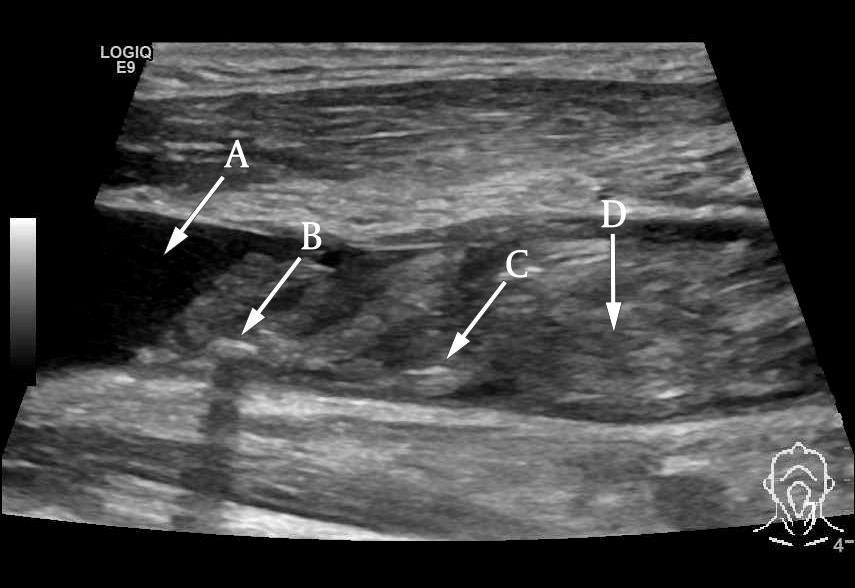

Ultralydundersøkelsen av halsen viste imidlertid en betydelig trombemasse som nærmest totalokkluderte venstre v. jugularis interna og v. subclavia (figur 1 og 2). Den totale utbredelsen av tromben kunne ikke fremstilles med ultralyd, og det ble derfor supplert med en CT-venografi, som viste utbredt trombosering som omfattet nedre del av venstre v. jugularis (fra nivå med carotisbifurkaturen), v. subclavia og v. brachiocephalica frem til innløpet av v. cava superior (figur 3). Det var multiple luftbobler fordelt i trombemassen. Vi mistenkte at dette var forårsaket av bakterier, og dermed at en infisert trombe var fokus for pasientens infeksjon.

Ultralyd er en ikke-invasiv og kostnadseffektiv metode for å påvise trombemasser. Dessverre er den suboptimal for diagnostikk av tromber lokalisert dypt under mandibula eller clavicula. CT-venografi er derfor av mange anbefalt som foretrukket undersøkelsesmetode (6). I vårt tilfelle fikk vi med CT-venografi identifisert hele utbredelsen av trombemassen samt påvist karakteristiske luftbobler som underbygget mistanken om infisert trombe.

Vi kan ikke med sikkerhet fastslå når i forløpet trombemassene utviklet seg hos vår pasient. Vi vet at han under intensivbehandlingen for sin ileusrelaterte sepsis fikk påvist dyp venetrombose i høyre v. iliaca communis. Mest sannsynlig ble også trombene ved veneportkatetret utviklet rundt dette tidspunktet. Det er mindre sannsynlig at de ble dannet senere under pågående terapeutisk behandling med dalteparin, selv om pasienten hadde forhøyet tromboserisiko som følge av underliggende malignitet. Da veneporten igjen ble tatt i bruk til væske og parenteral ernæring på sengepost, fikk vi ikke aspirert blod, men kunne lett injisere væske. Hadde vi her tatt ultralyd av karet, kunne vi kanskje sett trombemasse i venen, og ikke en fibrinhylse, som vi antok var årsaken til aspirasjonsproblemene.